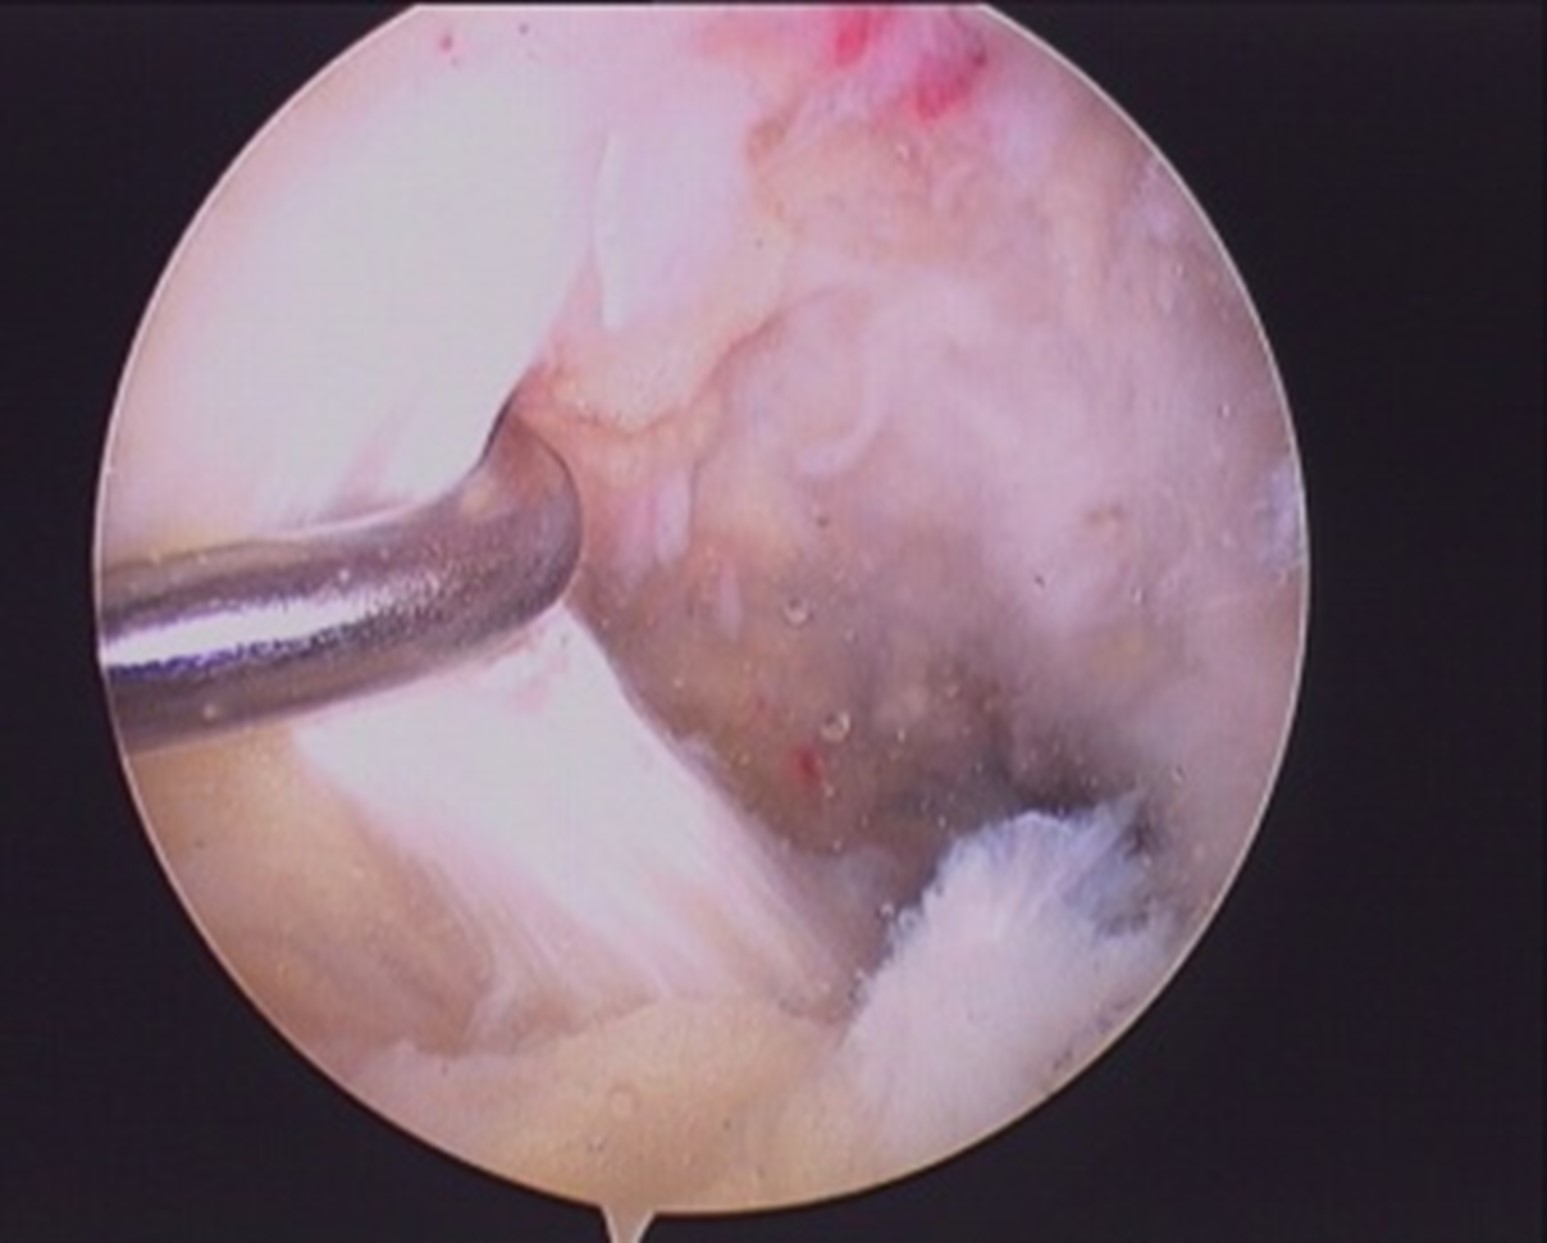

- PCL is wrapped with suture loop (Arthrex fibrewire no 2/orthocoat) by passing the suture ends from both windows(bare area in between ACL and PCL,area between medial femoral condyle and PCL).fig 1,2.

- Both ends of the suture loop are delivered posteriorly through inferior PM portal and sliding knot is passed and sitted over the osseo-ligamentous fragment.fig 3, 4.